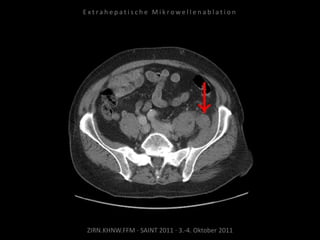

Metastase medial des linken

Musculus iliacus:

1 Nadelposition.

Kontrollbildgebung:

CT 18.08.2010

MRT 08.09.2010

Restvitalität von 2 Metastasen.

Nadelposition unzureichend?